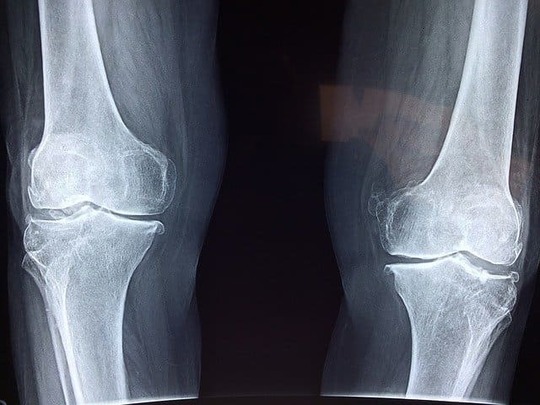

症候性肋間神経痛は明確に原因があって起きる肋間神経痛です。症候性肋間神経痛の原因は、変形性脊椎症や胸椎椎間板ヘルニア、脊椎腫瘍などの脊椎に原因があるケースと、肋骨の骨折や肋骨の腫瘍が原因となるケースがあります。

椎間板ヘルニア、脊椎の変形、肋骨の骨折・ひびなど。